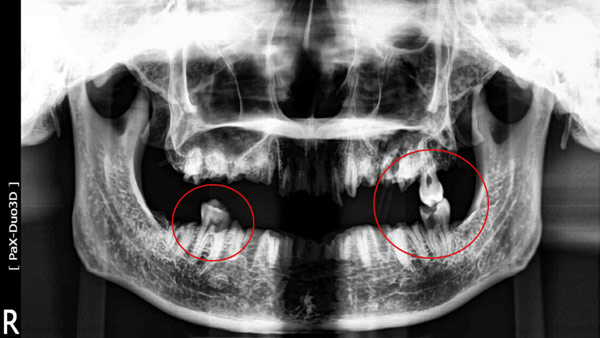

인천 계양경찰서가 공개한 사진에 따르면 훼손된 시신 두개골에 치아가 3개만 남아 있고 위턱 왼쪽 치아에는 금 인레이, 아래턱 왼쪽과 오른쪽 치아에는 레진 치료를 한 흔적이 남아 있습니다.

경찰은 사진에 나오는 치아 3개를 제외한 나머지 치아 상당수는 기계 등에 의해 고의적으로 훼손된 것으로 추정했습니다.